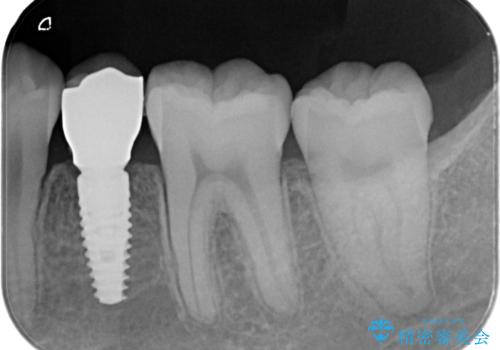

小臼歯のインプラント

- 小臼歯が先天性欠損していたため、インプラントにて補綴しています。

当院ではストローマンインプラントを導入しています。